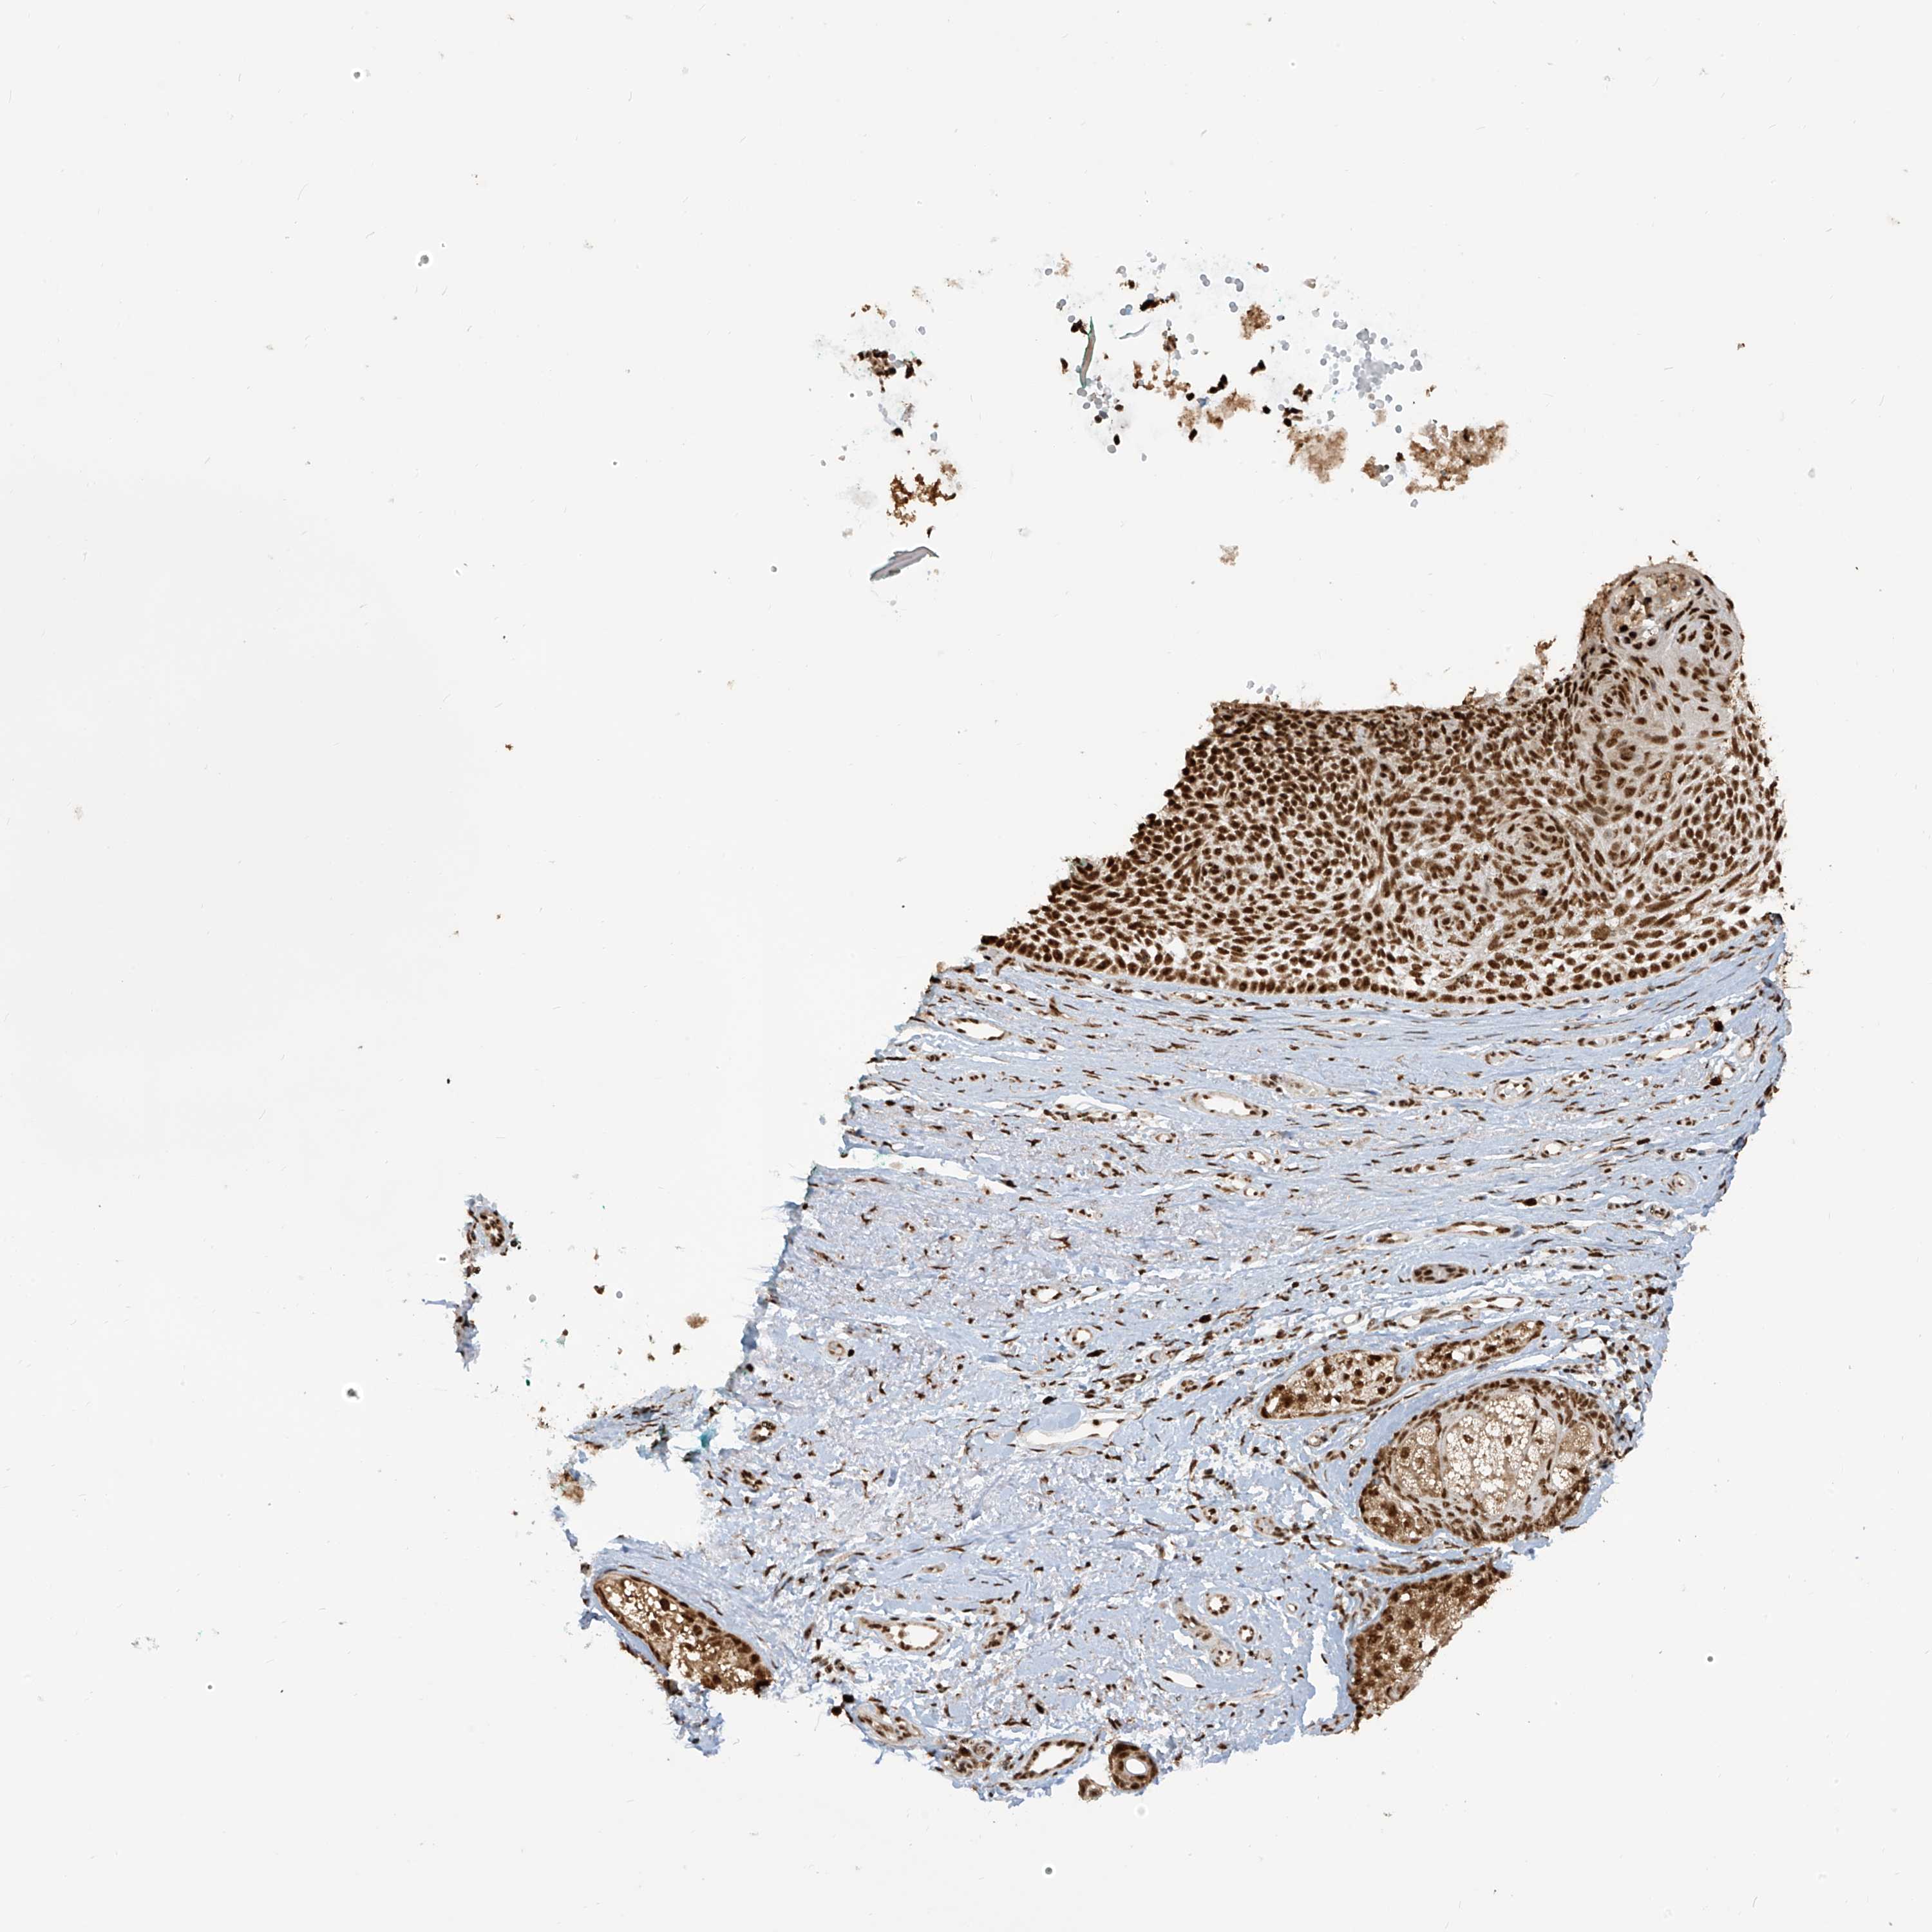

SKIN CANCER - Protein expressioni

A mouse-over function shows sample information and annotation data. Click on an image to view it in a full screen mode. Samples can be filtered based on level of antibody staining by selecting one or several of the following categories: high, medium, low and not detected. The assay and annotation is described here.

Each image is clickable and will lead to virtual microscopy that enables deeper exploration of all samples and also displays staining intensity scores, fraction scores and subcellular localization as well as patient and tissue information for each sample.

Antibody HPA034669

Staining

Medium

Intensity

Moderate

Quantity

75%-25%

Location

Cytoplasmic/membranous,nuclear

Squamous cell carcinoma, NOS